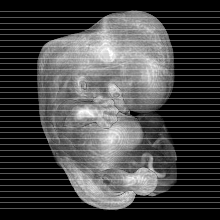

Carnegie Stage 18 (44 post-ovulatory days)

Most embryos at stage 18 are approximately 44 postovulatory days old and measure 13-17 mm in length. Distinguishing criteria for this stage include cervical and lumbar flexures, distinct notching in the hand plate, the first appearance of the elbow, eyelid folds may appear in more advanced specimens, and auricular hillocks begin to form distinct parts of the external ear.

MRI Slice Selector